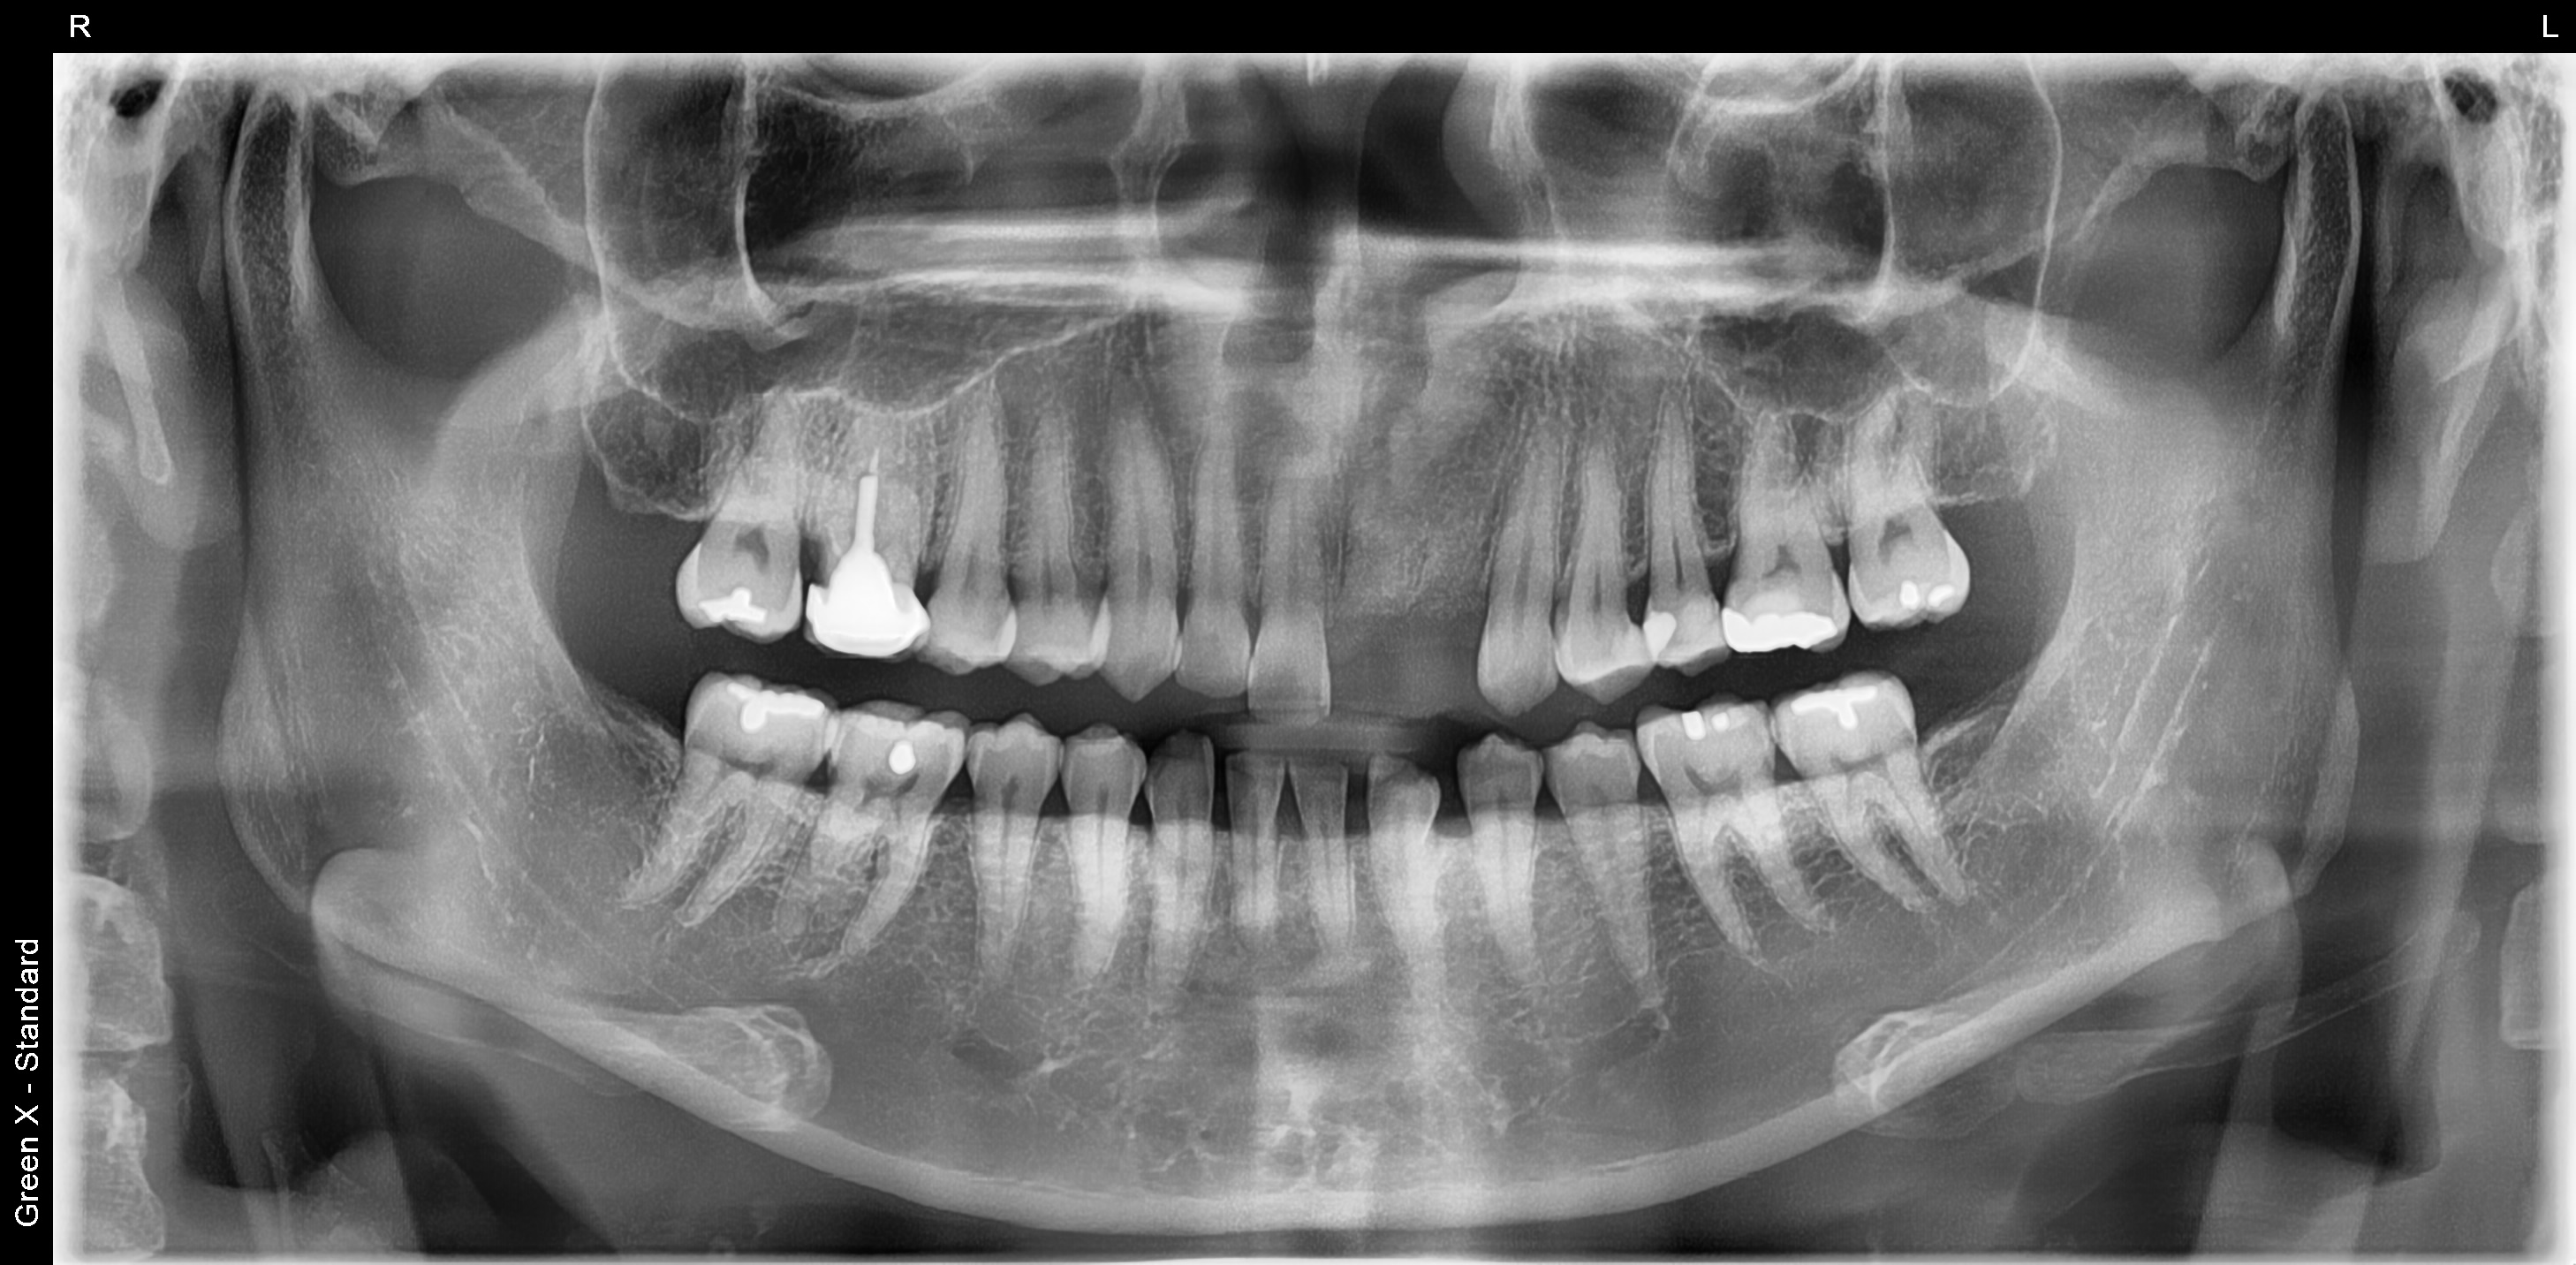

김포에거주하시는 30대 여성분이 앞니가 부러져서 서울케이치과에 내원하셨습니다.

엑스레이 사진을 찍어보니 앞니 2개의 뿌리에 염증이 심하여 발치 당일 잇몸뼈 보존을 위하여 치조골 이식술을 먼저 진행하였습니다.